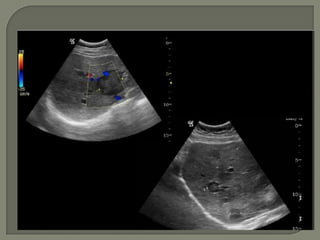

   Similar aspecto a las hipovasculares, pero con

flujo importante a la valoración con Doppler color y

muchas veces son ecogénicas.

Subgrupo de lesiones metástasis con importante aportevascular.  Similar aspecto a las hipovasculares, pero con flujo importante a la valoración con Doppler color y muchas veces son ecogénicas.  Lostumores primarios con implantes hepáticos hipervasculares mas frecuentes : • Neuroendocrinos, sarcomas, células renales y melanoma. • Neuroendocrinas: diferencial con hemangiomas • Metástasis de melanomas: usualmente con sangrado